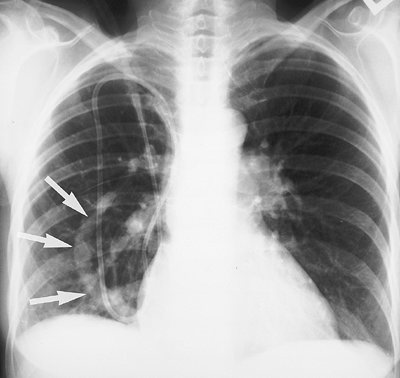

Bronchopulmonary sequestration consists of nonfunctioning lung tissue, usually cystic and often masslike, that has an anomalous systemic blood supply, usually from the aorta, and no normal communication with the tracheobronchial tree. This disorder is classified into two types: intralobar (the more common type) and extralobar (4). Both types occur most commonly in the posterior basal segment of a lower lobe, usually on the left. Intralobar sequestration is contiguous with normal lung parenchyma, has no separate pleural investment, receives arterial supply most commonly from the aorta, has venous drainage most commonly into a pulmonary vein, and is only rarely associated with other anomalies (Figs. 16-2 and 16-3). Extralobar sequestration is related to a hemidiaphragm (usually the left), and it is often situated between the inferior surface of the lower lobe and the diaphragm, or below the diaphragm. It has a pleural investment separate from the rest of the lung; receives arterial supply from the aorta but usually has venous drainage into the systemic venous system (e.g., inferior vena cava, azygos vein, or portal vein); and is often associated with other congenital anomalies (most commonly eventration or paralysis of the ipsilateral diaphragm and left diaphragmatic hernia) (Fig. 16-4). The classic radiographic appearance of pulmonary sequestration is recurrent or persistent abnormal opacity in a lower lobe that never completely clears. The diagnosis can be confirmed by showing the systemic arterial supply, either with magnetic resonance imaging or CT angiography (5). In adults, this disorder is often discovered incidentally.

FIGURE 16-7. Pulmonary venolobar syndrome. PA chest radiograph of a 56-year-old woman shows the anomalous draining vein (scimitar; arrows), diminutive right pulmonary artery, and relatively small right lung.